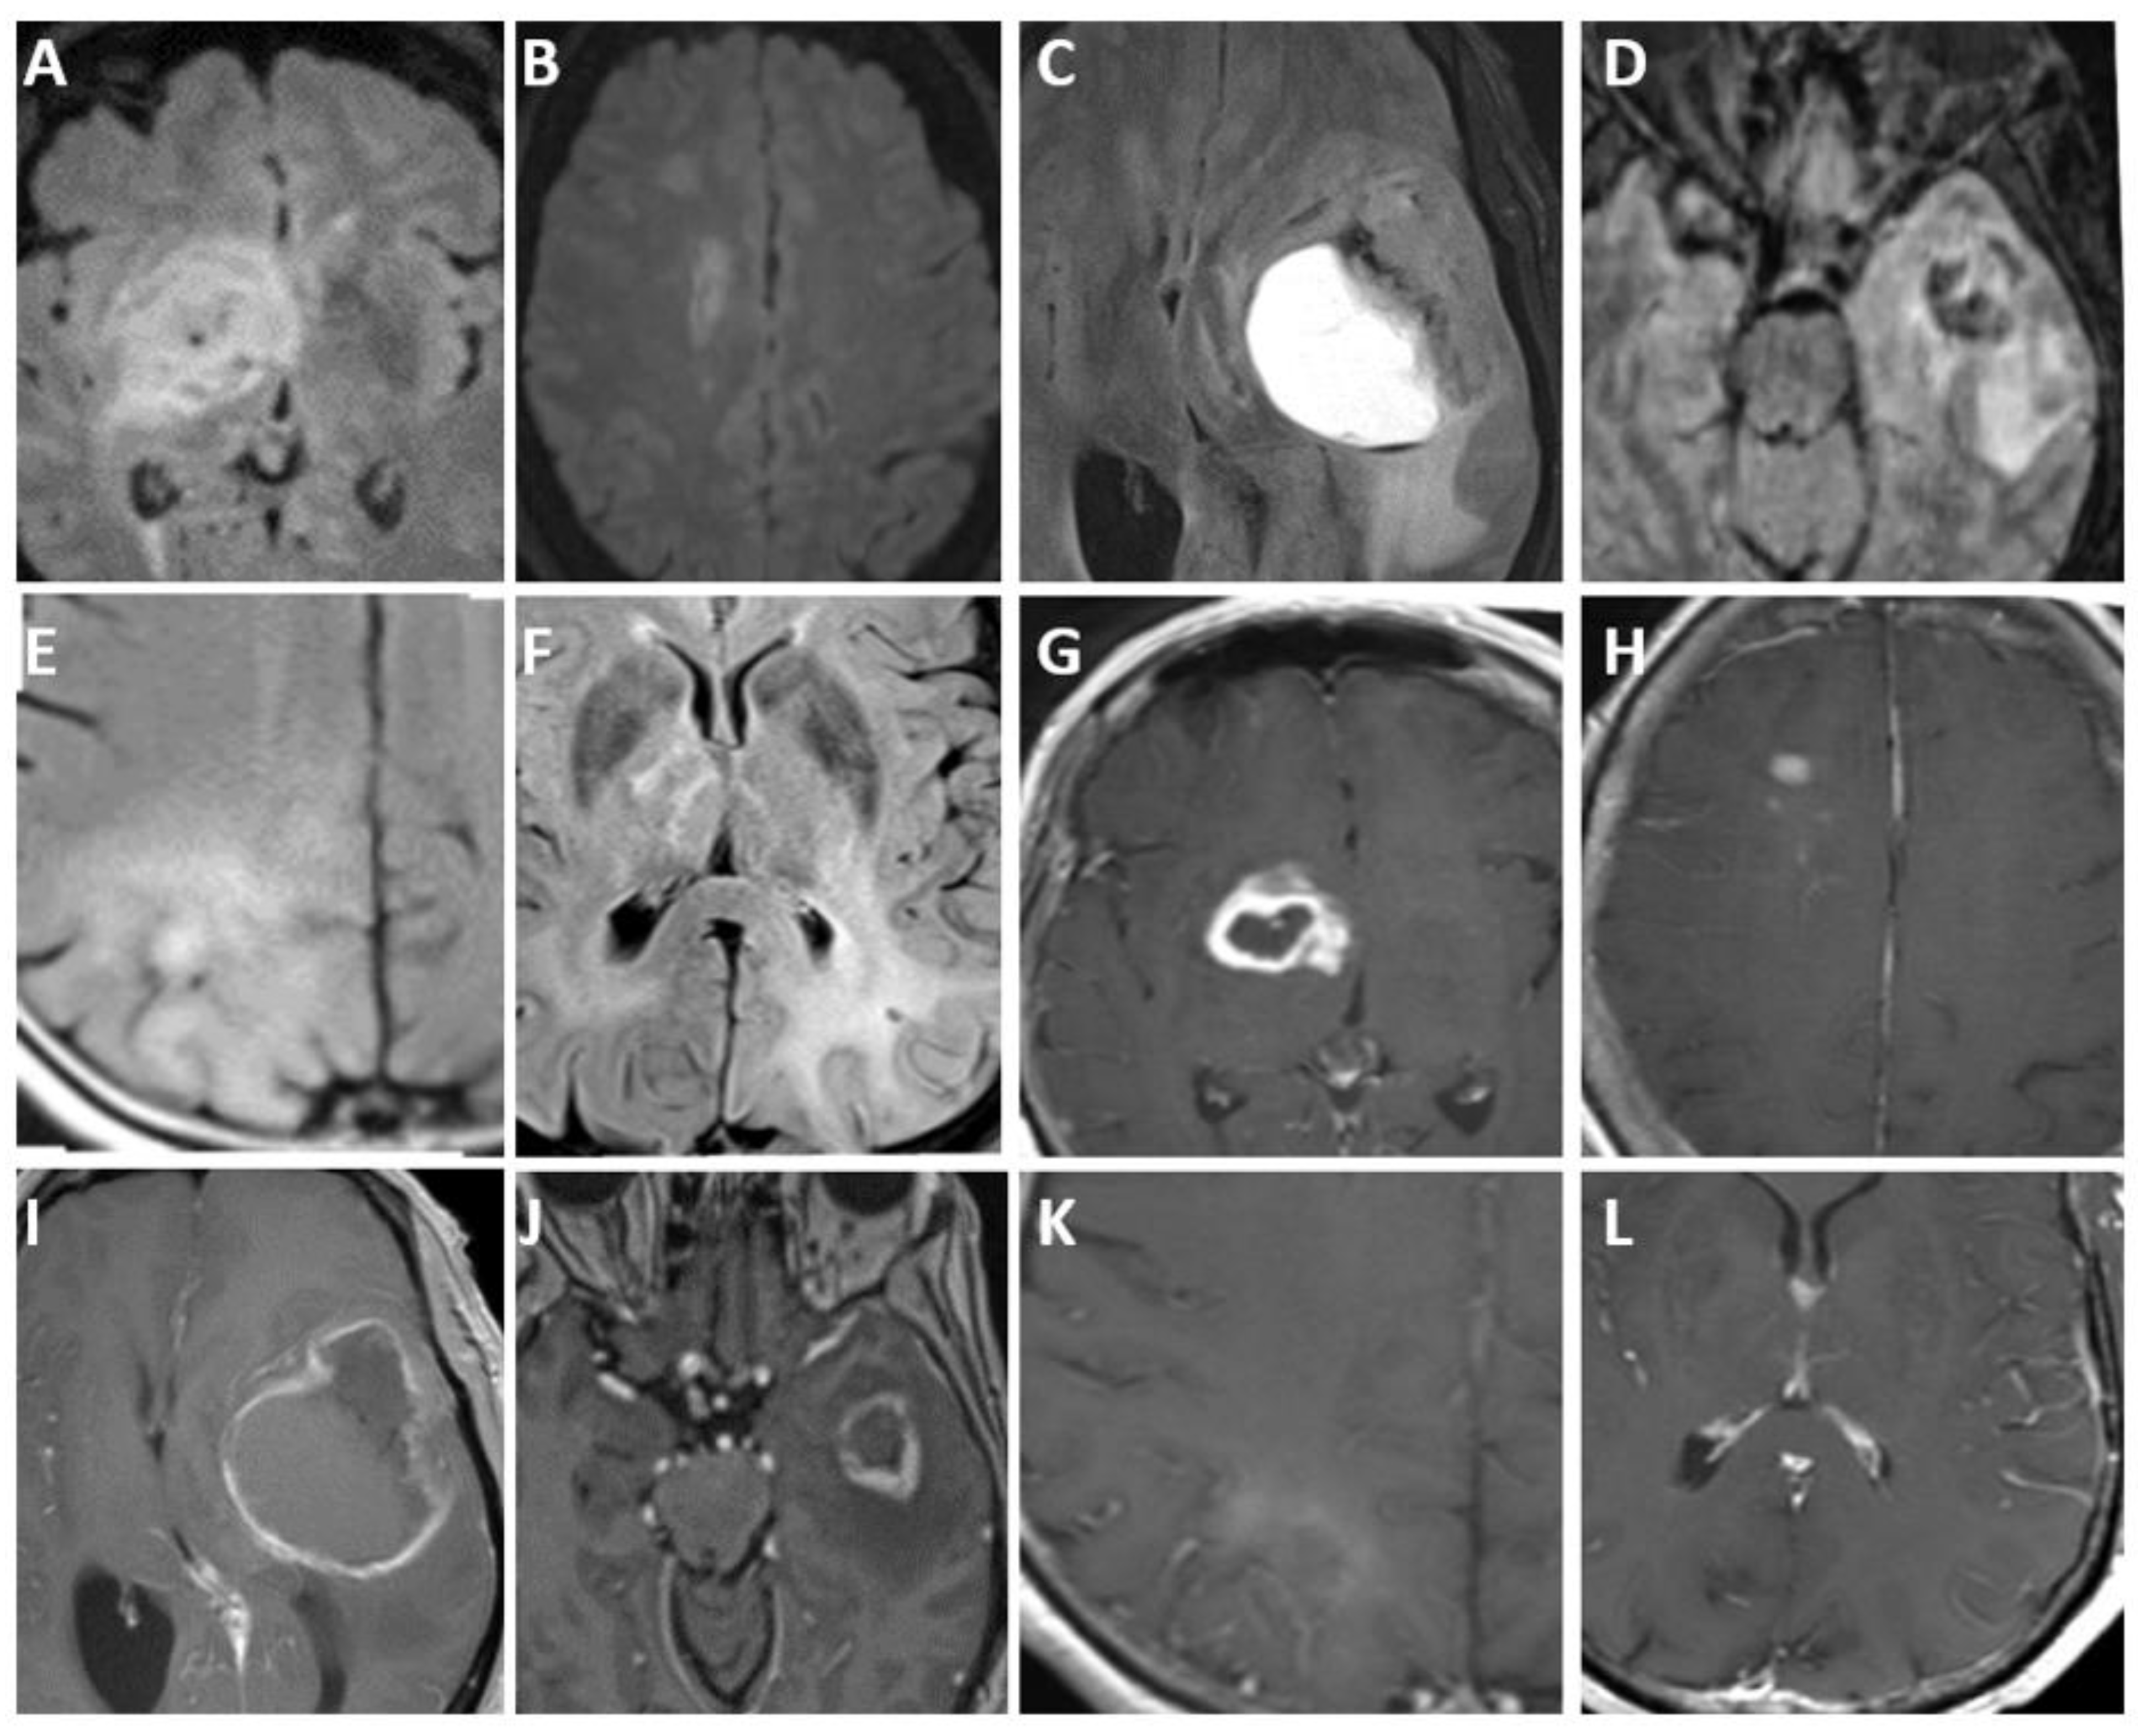

- Kurokawa, R.; Baba, A.; Kurokawa, M.; Pinarbasi, E.S.; Makise, N.; Ota, Y.; Kim, J.; Srinivasan, A.; Moritani, T. Neuroimaging features of diffuse hemispheric glioma, H3 G34-mutant: A case series and systematic review. J. Neuroimaging 2022, 32, 17–27. [Google Scholar] [CrossRef] [PubMed]

- Vettermann, F.J.; Felsberg, J.; Reifenberger, G.; Hasselblatt, M.; Forbrig, R.; Berding, G.; la Fougère, C.; Galldiks, N.; Schittenhelm, J.; Weis, J.; et al. Characterization of Diffuse Gliomas With Histone H3-G34 Mutation by MRI and Dynamic 18F-FET PET. Clin. Nucl. Med. 2018, 43, 895–898. [Google Scholar] [CrossRef]

- Soni, N.; Agarwal, A.; Ajmera, P.; Mehta, P.; Gupta, V.; Vibhute, M.; Gubbiotti, M.; Mark, I.T.; Messina, S.A.; Mohan, S.; et al. High-Grade Astrocytoma with Piloid Features: A Dual Institutional Review of Imaging Findings of a Novel Entity. Am. J. Neuroradiol. 2024, 45, 468–474. [Google Scholar] [CrossRef]

| Diffuse hemispheric glioma, H3 G34-mutant | H3 G34, TP53, ATRX | Newly recognized | Unifocal, cortex, ependymal and/or leptomeningeal contact. |

| Diffuse pediatric-type high-grade glioma, H3-wildtype, and IDH-wildtype | No IDH or H3 mutations, PDGFRA, MYCN, EGFR | Newly recognized | Heterogeneous, akin to other high-grade gliomas. |